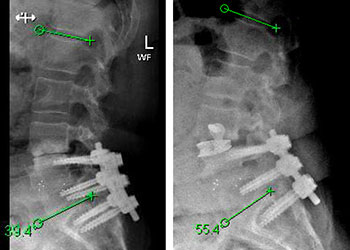

Spine:

Central Cord Syndrome

Author: Yusef Imani M.D., F.A.A.N.S., Read More!